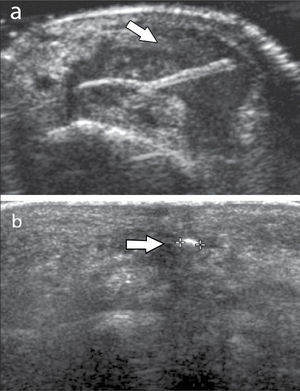

En operadores entrenados (8) permite una buena evaluación de los tendones del manguito rotador, incluso comparable con la RM (9) en busca de tendinosis, tendinopatía cálcica y roturas (figuras 2-4).

En el tendón de la porción larga del biceps es útil para estudio de tenosinovitis o luxación. En articulación acromioclavicular podemos encontrar compromiso degenerativo o inflamatorio, derrame, quistes periarticulares o signos indirectos de disyunción. Se visualiza el receso articular glenohumeral posterior en búsqueda de derrame y también los planos musculares periarticulares. La bursitis subacromiodeltoidea se manifiesta como engrosamiento y/o líquido en la bursa (figura 5). La evaluación dinámica permite observar fenómenos de pinzamiento por el ligamento coracoacromial y también pinzamiento subacromial a la bursa o los tendones.